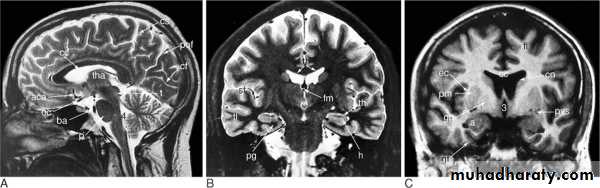

Sagittal coronal

MRI